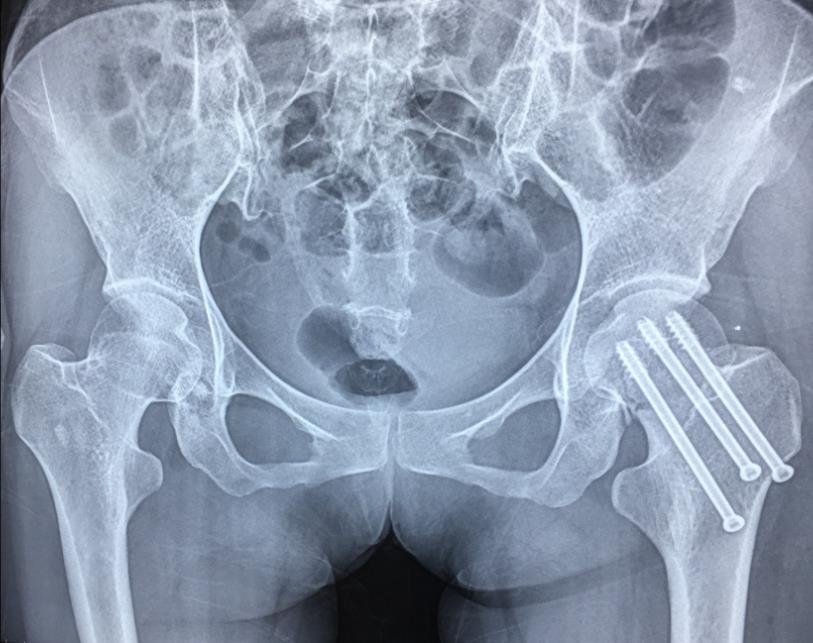

闭合复位经皮固定手术步骤

1、经皮沿股骨颈轴线置入空心钉导针,确保导针平行;

2、标准放置螺钉为倒三角形,其中下方螺钉在股骨矩,后方螺钉在后方骨皮质、研究发现倒三角形平行三枚螺钉能提供最佳的固定强度;

3、螺钉位于股骨颈四周,特别是后侧及下方,避免低于小转子方向进针,可能导致术后转子下骨折;

4、两个平面透视导针位置良好后切开皮肤,空心钻铭孔,导针引导下拧入空心钉,空心钉确保所有螺纹位于骨折线近端,螺钉头应距离软骨下骨5mm。

空心钉固定的三原则:“贴边、平行、倒品”。

1、贴边是指3枚螺钉在股骨颈内,尽量靠近外围皮质。这样3枚螺钉作为一个整体,对整个骨折面可形成面状加压,如果3枚螺钉不够离散,更趋于点状加压,稳定性较差,不能较好地对抗扭转和剪切。

图1 3枚螺钉在股骨颈内的理想位置

图2 倒品字固定

3、平行生物力学更稳定。